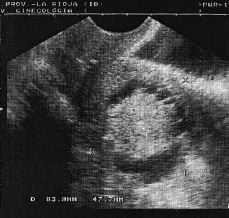

Acudió a revisiónpreventiva, detectándose por ecografía unútero de tamaño normal, cuya cavidad estaba ocupadapor una imagen hiperecogénica de 31 * 26 mm quelo hacía compatible con adenocarcinoma de endometrio opólipo residual calcificado. Los ovarios eranatróficos.

Figura1. Imagenecográfica del linfangioma de cuerpo uterino.

El caso presentado reúneinterés por el diagnóstico diferencial que implica elhallazgo ecográfico. La imagen ultrasónicahiperrefringente rodeada de un halo anecoico con tractos radialeshiperecoicos lo hacían compatible con un adenocarcinoma deendometrio o pólipo endometrial calcificado. Descartado elorigen endometrial por histeroscopia y ante la sospecha de tumormaligno miometrial, el estudio de la pieza concluyó que setrataba de una tumoración completamente benigna. En estesentido, el examen anatomopatológico fue el quedesenmascaró el diagnóstico, no teniendo quemodificar a su vez el plan terapéutico.